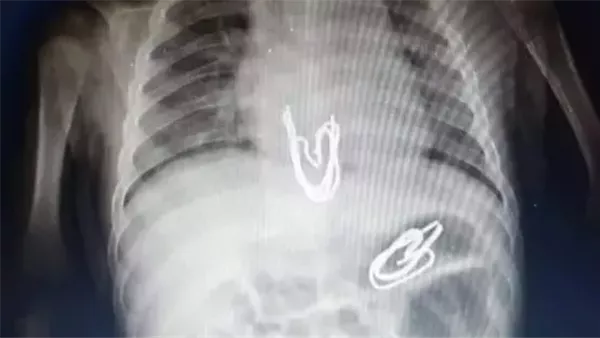

شهد مستشفى سوهاج الجامعي إنجازًا طبيًا جديدًا يُضاف إلى سجل نجاحاته في رعاية الأطفال، حيث تمكن فريق طبي متخصص من وحدة أمراض الجهاز الهضمي والكبد ومناظير الأطفال بقسم طب الأطفال من إجراء تدخل دقيق لاستخراج جسم غريب من معدة طفل يبلغ من العمر 4 سنوات، باستخدام منظار معدة مخصص للأطفال، دون الحاجة إلى تدخل جراحي، ووسط إجراءات دقيقة وآمنة.

وبحسب ما أعلنه المستشفى، فإن الحالة لطفل ابتلع دبوسًا معدنيًا، ما استدعى تدخلاً عاجلاً لإنقاذه. وبالفعل، نجح الفريق في استخراج الدبوس عبر المنظار، في إجراء استغرق وقتًا قصيرًا، دون حدوث أية مضاعفات أو آثار جانبية، ليغادر الطفل المستشفى بعد ثلاث ساعات فقط، وهو في حالة صحية مستقرة.